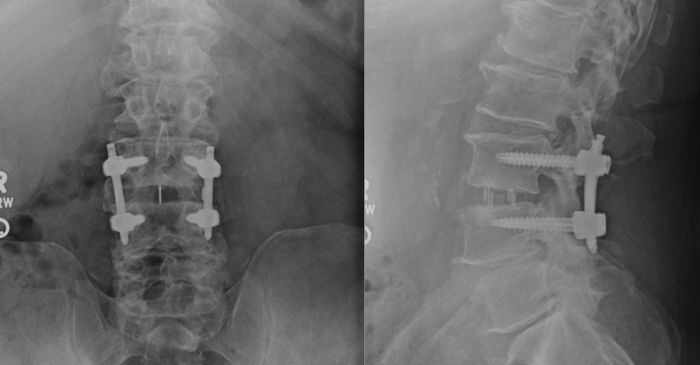

Transforaminal Lumbar Interbody Fusion (TLIF)

TLIF of Transforaminal Lumbar Interbody Fusion is a traditional open-surgical procedure aimed to remove pressure to the spinal nerves and provide stabilization of the spine bones (vertebrae) when there is abnormal motion between them.